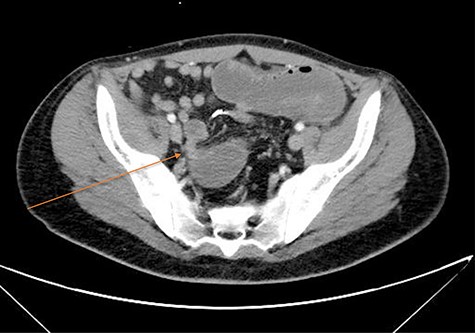

CT imaging demonstrating transition point in the pelvis at the level of the rectal stump; arrow marks transition point.

The patient represented to the emergency department on POD 6 with abdominal pain, nausea and an abrupt decrease and near cessation of ileostomy output. A computed tomography (CT) scan demonstrated acute high-grade small bowel obstruction with transition point within the pelvis at the site of the sigmoid resection (Fig. 1). The patient was treated with nasogastric tube decompression and intravenous hydration and was taken urgently to the operating for laparoscopic exploration. Upon entering the abdomen, dilated but viable small bowel loops were encountered. The dilated loops were traced to the pelvis where a dramatic transition to decompressed small bowel was found (Fig. 2). Here, an open staple on the corner of the rectal stump staple line caused tethering and obstruction of an adjacent small bowel loop (Fig. 2B). The staple was carefully released and removed from the peritoneal cavity. The transition point caused by the staple could easily be visualized following removal and there was no evidence of serosal injury or ischemia (Fig. 2C). Gas was observed to immediately fill the previously decompressed distal small bowel loops and no other sites of obstruction were identified. The patient had an uneventful postoperative course with immediate return of bowel function. He was discharged home 2 days following reoperation with no long-term sequelae.